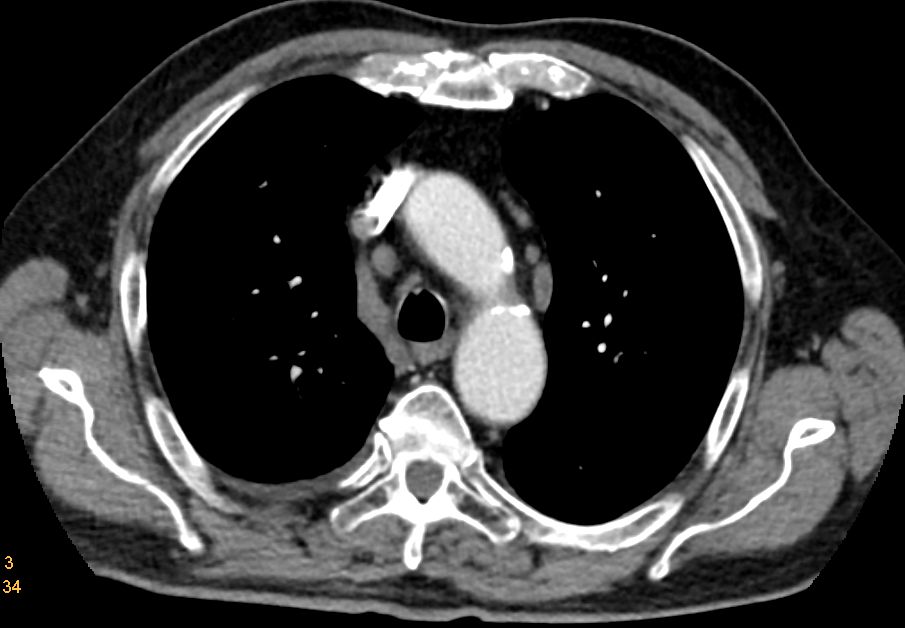

Lymphknoten - Metastasen

Links paraaortal Lymphknotenmetastasen. Zahlreiche mesenteriale Lymphknotenmetastasen.